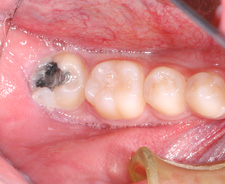

Redressement de molaires avec des mini-vis (1)

(A, B) Condition avant le redressement de la molaire.

(C) Mini-vis (recouverte de colle pour retenir un fil), quelques boîtiers et un élastique sont tout ce qui sera nécessaire pour redresser la molaire.